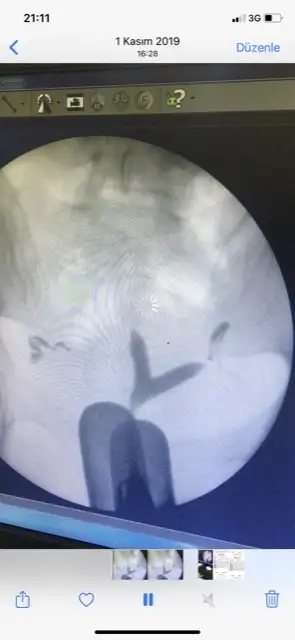

Canım mükemmel bir rahmin varKızlar rahim filmi sonrası doktor arka arkaya hasta alıyordu herşey yolunda dedi çıktım perde var mı Y ya da kalp şeklinde gibi riskli durum var mı soramadım anlayanlar bakabilir mi bir sorun gören var mı?

Canım mükemmel bir rahmin varbak tüp de açılmış inşallah kolayca gebe kalırsın artık, perde olunca böyle üçgen olmuyor yukardan içeriye doğru basık oluyor bak bu şekilde

Kalp şeklinde olunca ne oluyor ki benim kalp şeklinde rahminBiri tıkalı idi üç kere basınç tazzik ile açtı doktor sağ olsun canım umarım tıkanmamıştır tekrar peki canım rahim iyi mi sence y şeklinde kalp şeklinde falan değil demi ya da perdeli?